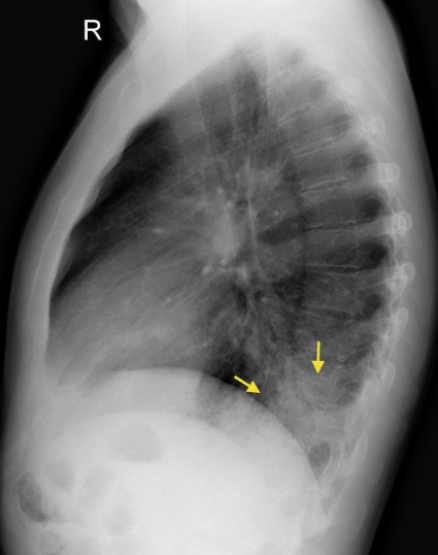

환자의 옆에서 촬영하게 되는 lateral view는 다음과 같은 뷰를 보여준다.

단순 chest PA에서 심장의 contour에 가려 잘 보이지 않은 병변이나, 폐에 생긴 병변의 위치를 3차원 적으로 파악할 수 있도록 도와줘 어느 폐엽에 병변이 생겼는지를 알 수 있도록 해준다. 위 사진에서는 좌측 폐, lower lobar pneumonia를 보여주는 사진이다.